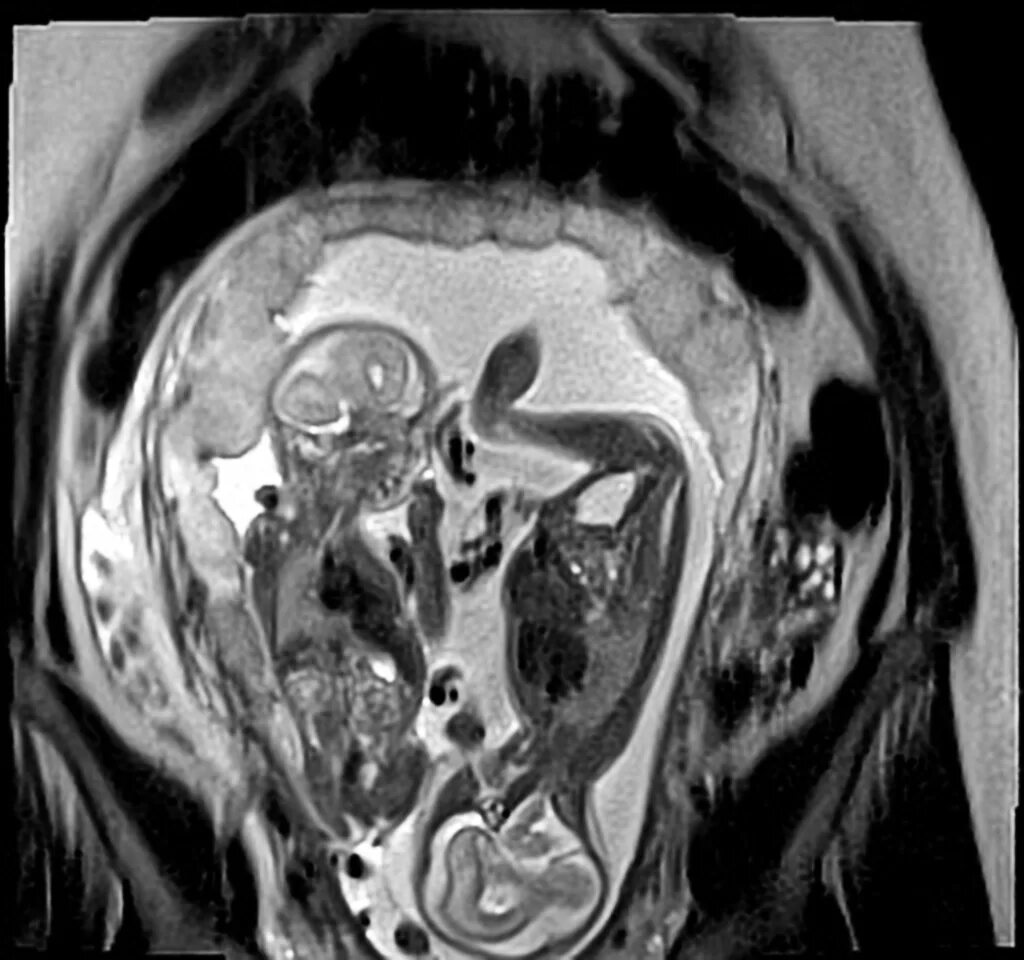

Делала рентген при беременности